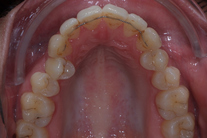

Tandreglering 1

Ung kvinna som tidigare haft tandreglering. Upplever inte att tänderna står i en fin tandbåge. 11 månaders behandling med genomskinliga Invisalignskenor resulterade i ett fint leende.